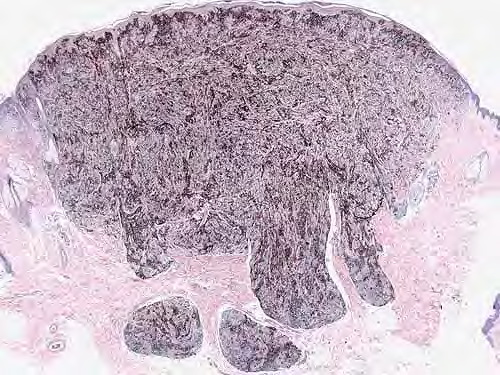

Pigmented Epithelioid Melanocytoma = ورم الخلايا الميلانية البشرواني المصطبغ